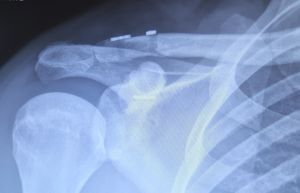

Abhängig vom Ausmaß der Verletzung und dem sportlichen Niveau des Patienten wird die Therapie entsprechend ausgerichtet. In leichten Fällen ist eine zeitlich begrenzte Ruhigstellung im Verband bis zur Schmerzfreiheit ausreichend. Bei ausgeprägteren Befunden oder sportlich aktiven Menschen sollte die operative Versorgung möglichst bald angestrebt werden. Heutzutage üblich ist die operative Versorgung mittels Fadenankersystem (AC-Tightrope). Bei dieser Versorgung ist kein Folgeeingriff oder Metallentfernung nötig. Eine Ruhigstellung ist bis zu sechs Wochen erforderlich.